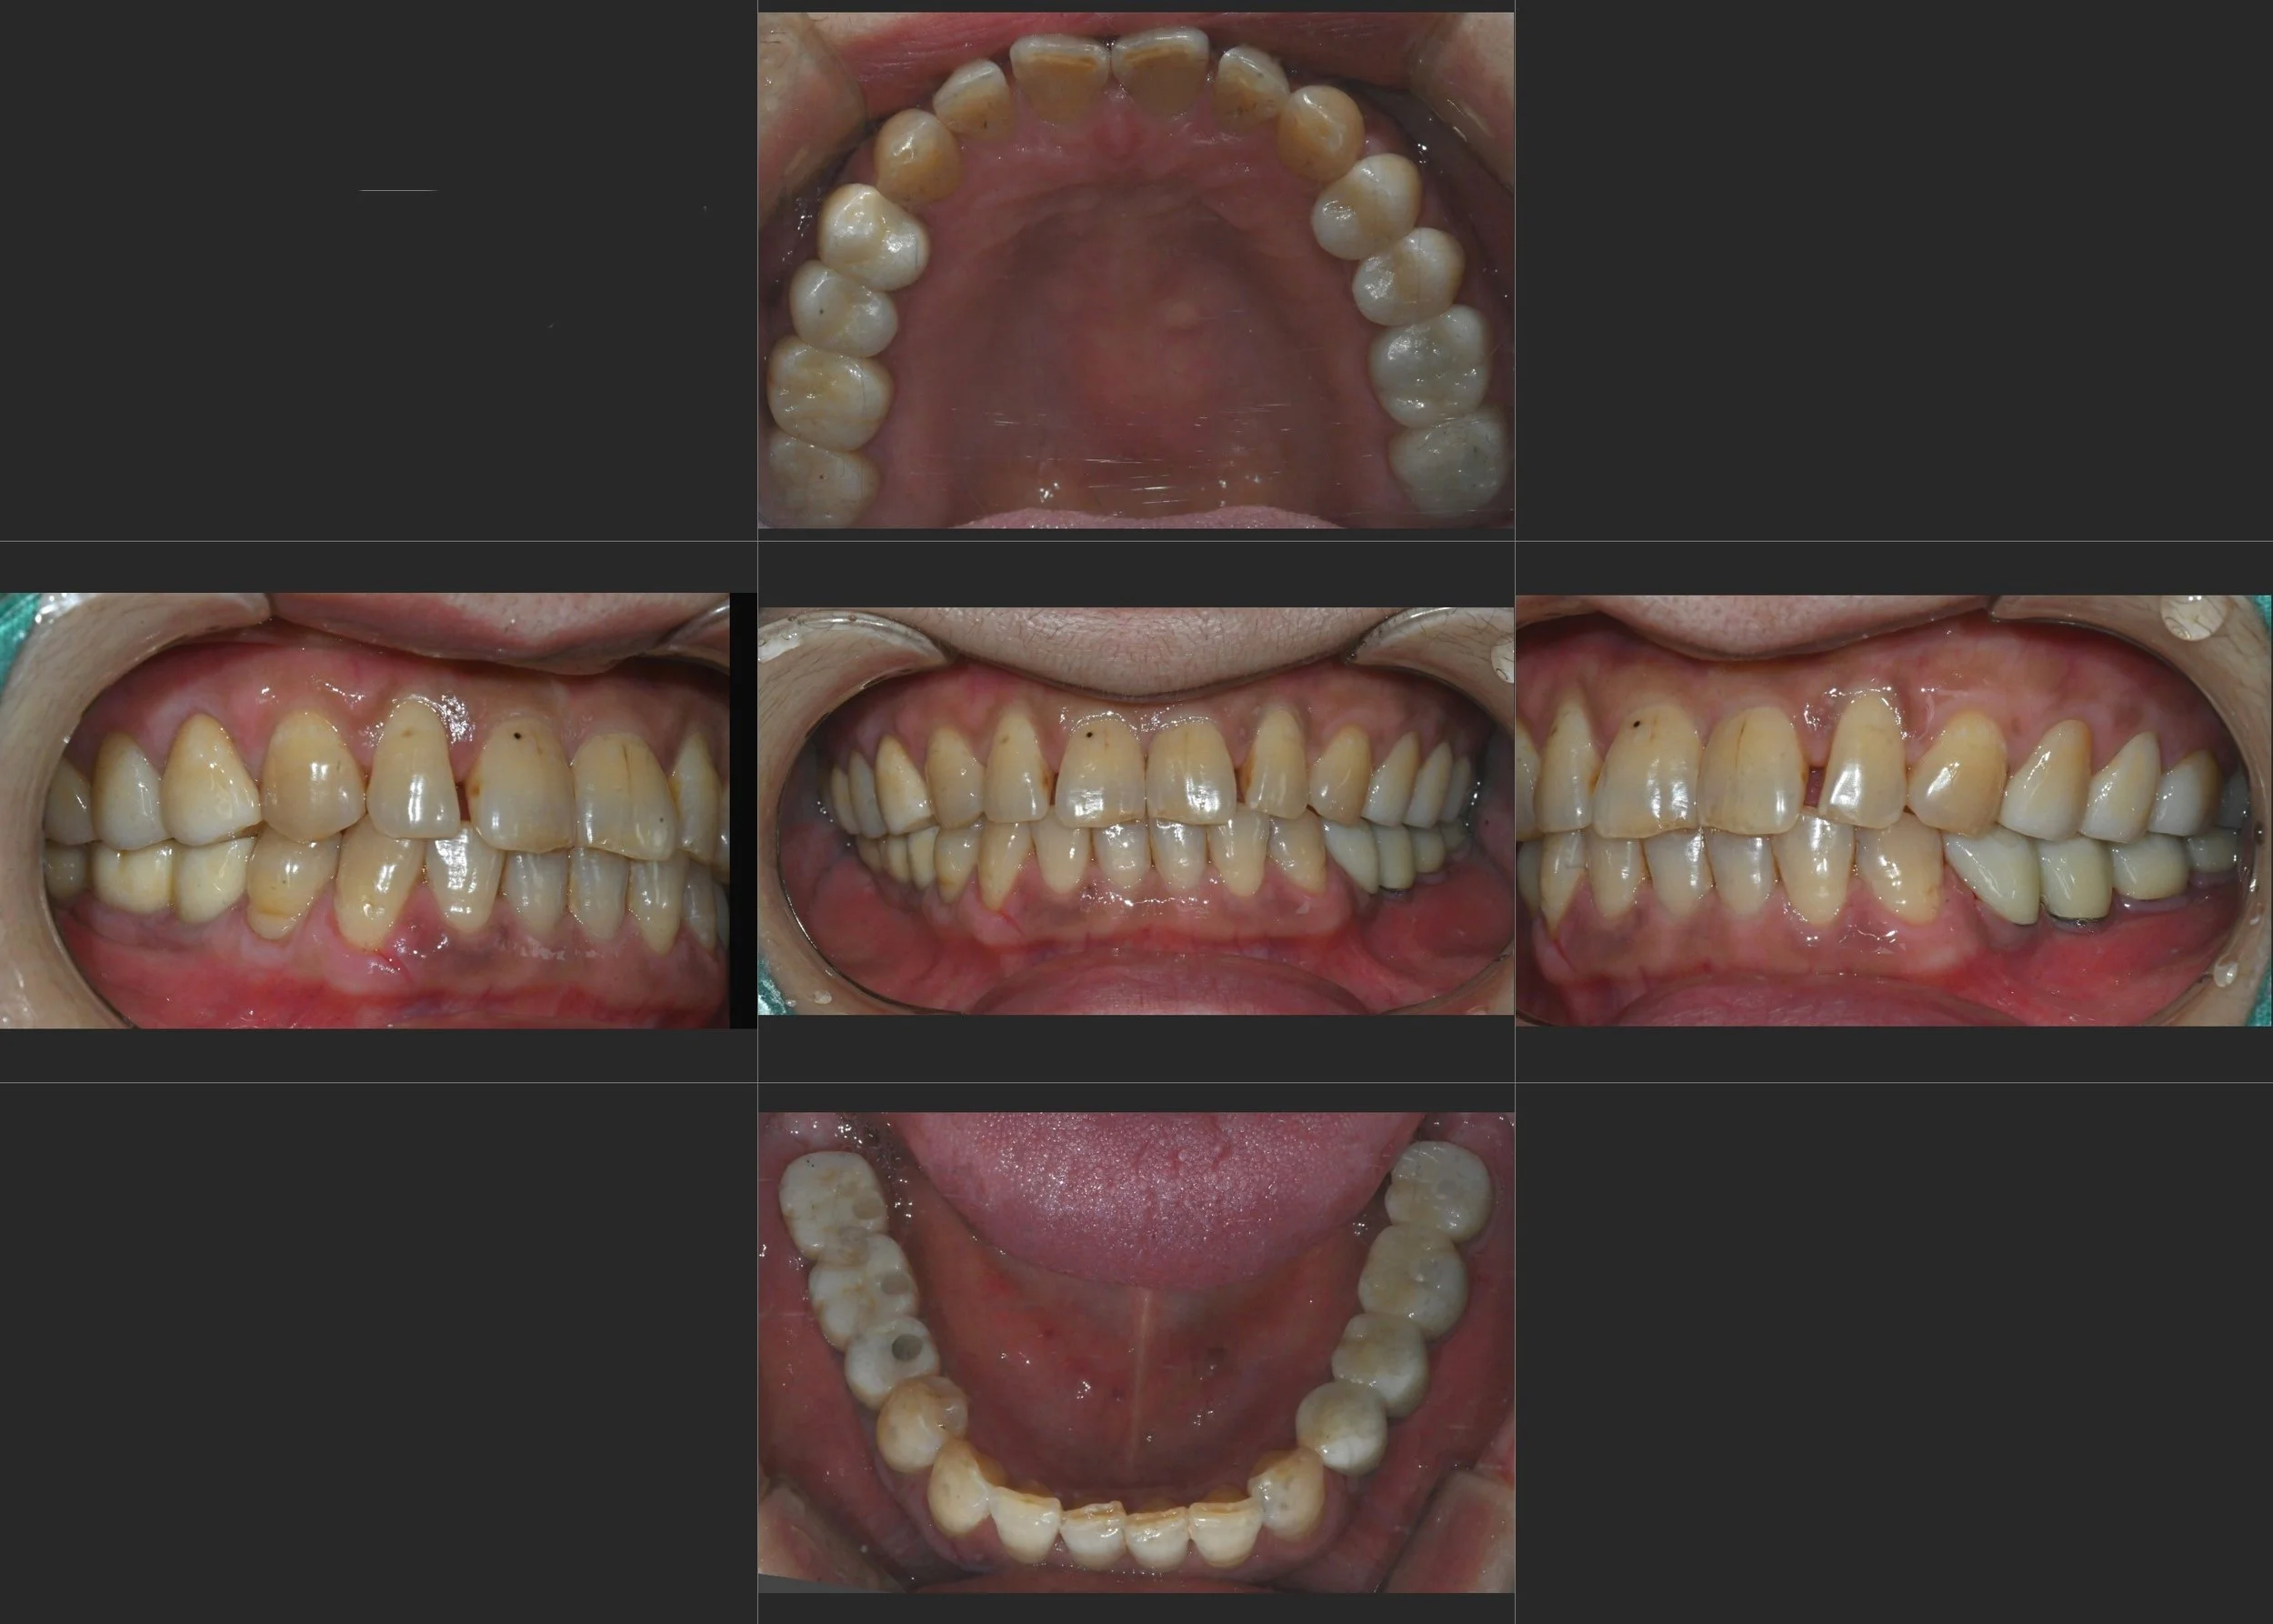

INTRA ORAL - BEFORE